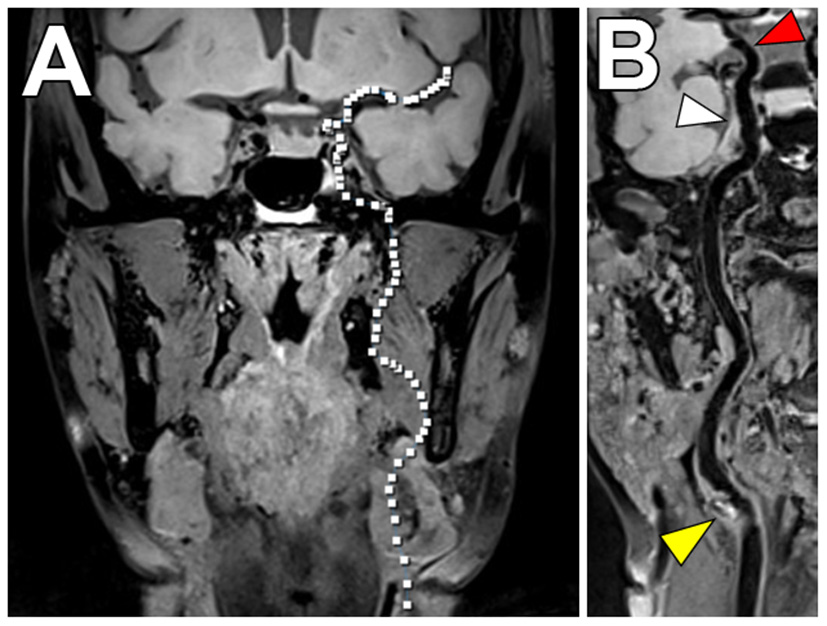

Many patients with vascular risk factors will have systemic atherosclerosis and have disease involving both the intracranial and cervical carotid arteries (91). To address this, investigators have proposed VW-MRI pulse sequences that permit joint intracranial and extracranial artery evaluation (Figure 8). Technical considerations for these pulse sequences include attention to the (1) needed spatial resolution to evaluate the smaller intracranial artery walls compared to the extracranial carotid artery walls, (2) need for adequate cerebrospinal fluid suppression around the circle of Willis compared to fat suppression around the carotid arteries, and (3) head/neck coils that allow adequate coverage. These innovative joint intracranial-extracranial VW-MRI pulse sequences provide promise in identifying the culprit source of stroke in vulnerable patients with systemic atherosclerosis and multiple potential sources of stroke (92–95).

Figure 8

Joint VW-MRI of the extracranial and intracranial arteries. (A) Coronal precontrast VW-MRI image shows the coverage of the joint intracranial and extracranial VW-MR image. (B) A curved reformatted image of the left cervico-cranial carotid artery shows intrinsic T1 hyperintense signal at the carotid bulb (yellow arrowhead), which was favored to be the culprit source of plaque in this patient with ischemic strokes. The intracranial internal carotid artery at the siphon (white arrowhead) and M1 middle cerebral artery segment (red arrowhead) showed no significant wall thickening to suggest intracranial atherosclerosis.